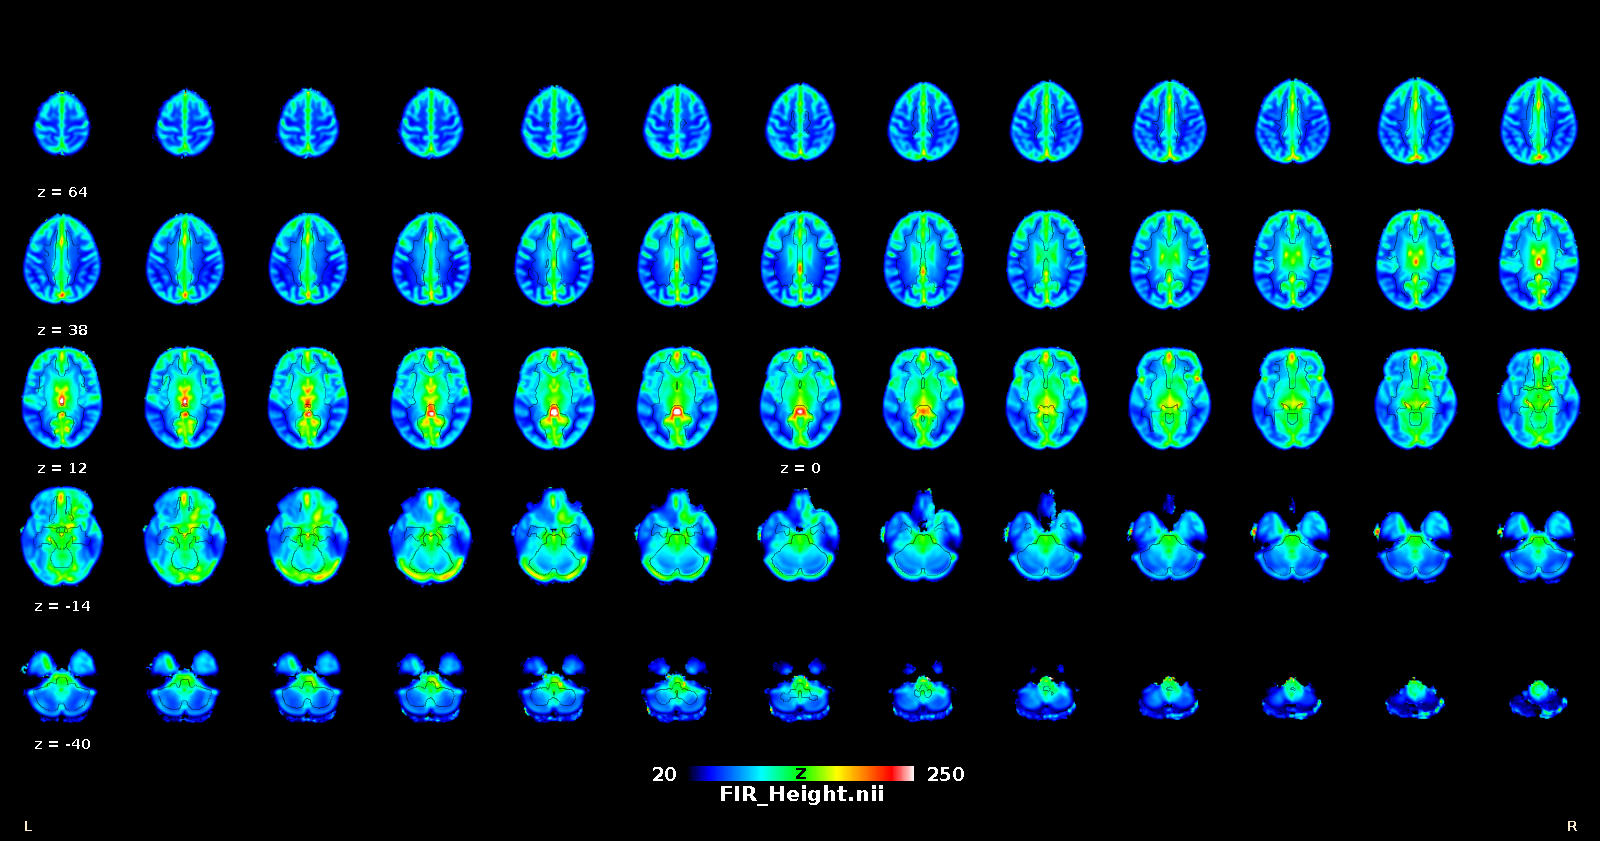

This toolbox is aimed to retrieve the onsets of pseudo-events triggering an hemodynamic response from resting state fMRI BOLD voxel-wise signal. It is based on point process theory, and fits a model to retrieve the optimal lag between the events and the HRF onset, as well as the HRF shape, using a choice of basis functions (the canonical shape with two derivatives, (smoothed) Finite Impulse Response, mixture of gammas).

Once that the HRF has been retrieved for each voxel, it can be deconvolved from the time series (for example to improve lag-based connectivity estimates), or one can map the shape parameters everywhere in the brain (including white matter), and use the shape as a pathophysiological indicator.